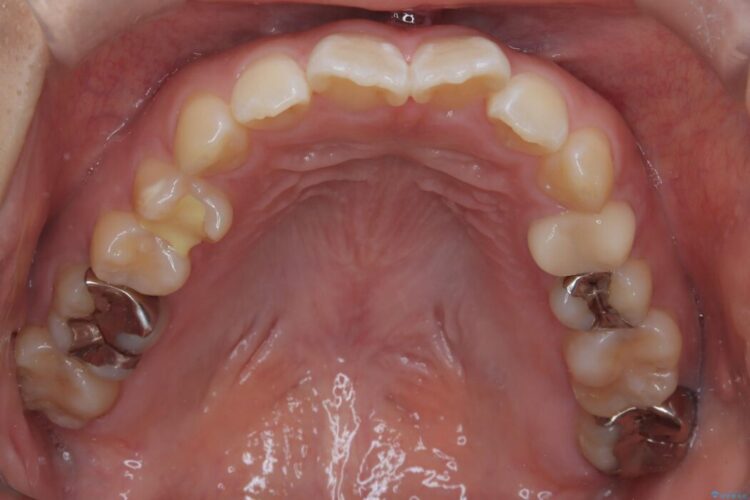

精密検査の結果、前歯を大きく後退させるスペースが必要と診断しました。

「前歯を下げたい」という患者様の強いご希望に応えるため、上下左右の第一小臼歯を抜歯。そのスペースを利用し前歯を奥へ移動させる治療計画を立案しました。

装置は人目を気にせず治療できるよう、上顎に裏側矯正、下顎に表側矯正を組み合わせたハーフリンガル矯正を提案しました。